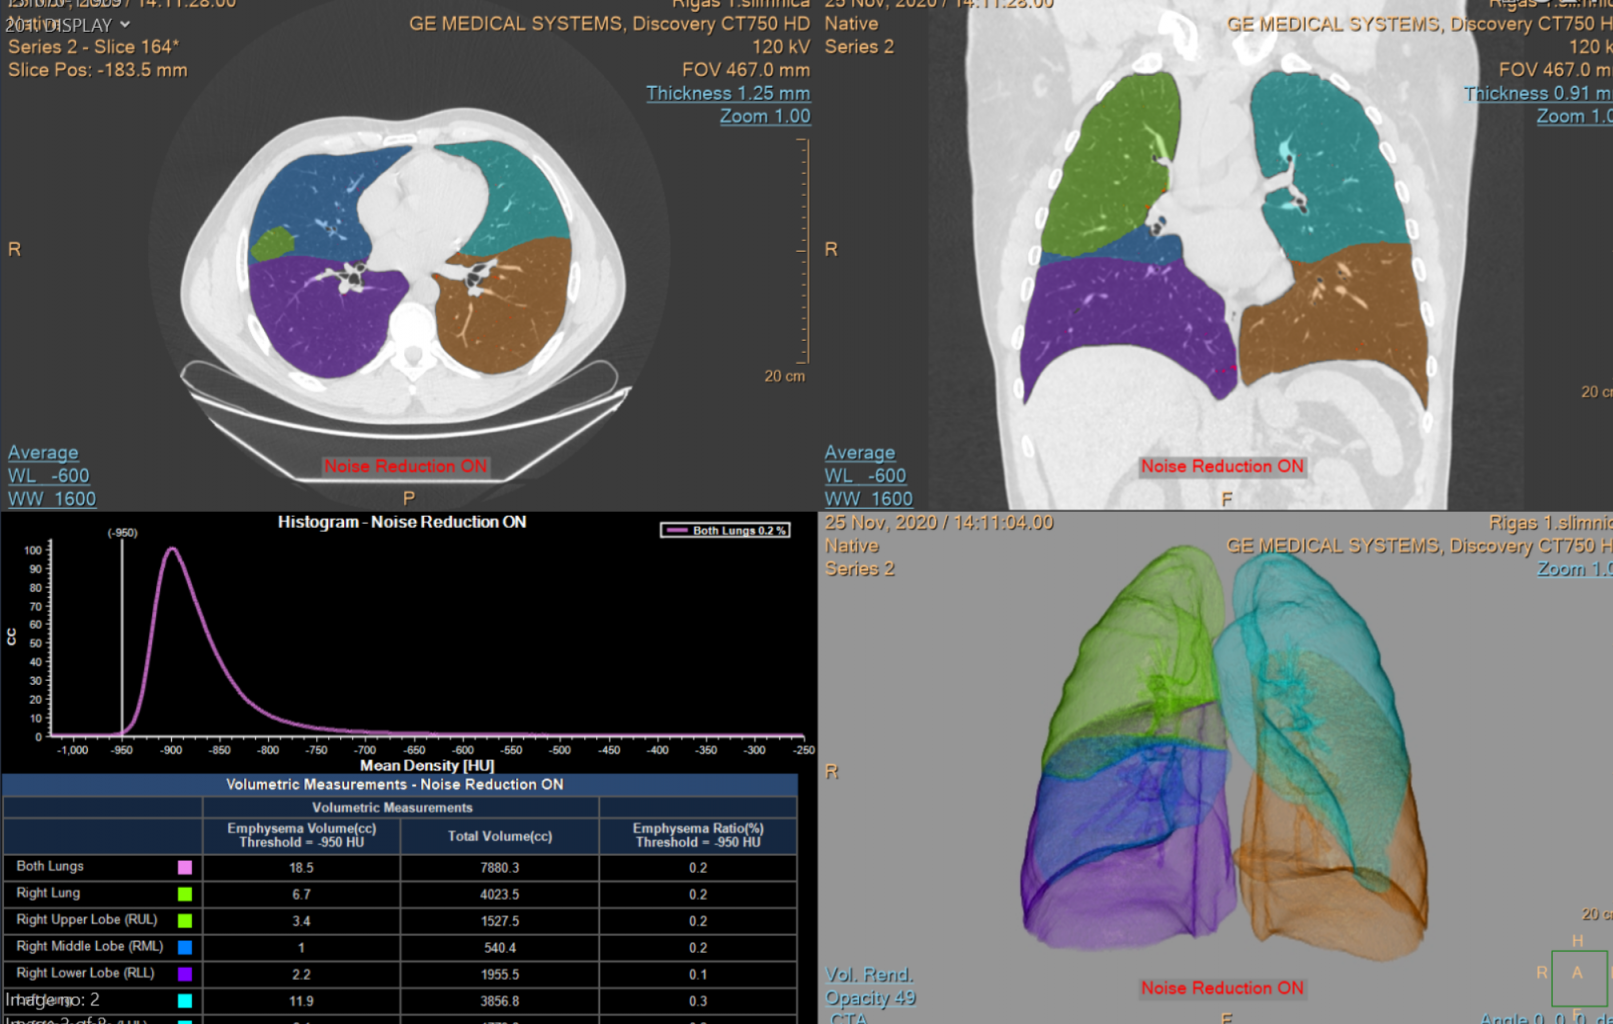

Ņemot vērā, ka SARS-CoV-2 skar daudzus pacientu orgānus, darba ietvaros pacientiem, kuri pārslimojuši COVID-19 infekciju tika veikti krūšu kurvja datortomogrāfijas bez kontrasta izmeklējumi ar 64 slāņu datortomogrāfu ar standarta izmeklēšanas protokolu, un augstas rezolūcijas izmeklējumu potenciāli bojāto plaušu audu rajonam, visiem pētījuma dalībniekiem veikti MR ar 3 Tesla stipru magnētiskā lauka aparātu vēdera dobuma orgāniem, lai diagnosticētu iespējamos bojājumus parenhimatozos orgānos, izmantojot standarta izmeklēšanas sekvences (FSE T2; FSE T1; SPGR in phase, out phase) un difūzijas uzsvērto attēlu (DWI), ar dažādām pieaugošām b vērtībām (50; 200; 800; 1000; 2000), kā arī šķietamā difūzijas koeficienta noteikšanu (ADC). Veikti US izmeklējumi vēdera dobuma orgāniem, limfmezgliem, lai diagnosticētu dažādus COVID-19 izraisītu aknu, nieru un liesas bojājumus, izmantojot standarta izmeklēšanas režīmus (B režīms, krāsu doplerogrāfija) un papildus veikta multiparametriska aknu izvērtēšana ar elastogrāfiju, izmantojot US šķērsviļņu metodi (2D SWE), vērtējot padziļināti aknu fibrozes un viskozitātes pazīmes kvantitatīvi, kā arī steatozes pakāpi. Radioloģiskā atradne tika korelēta ar laboratorisko atradi un klīniskiem datiem.

Projekta ietvaros atklāts, ka COVID-19 pārslimojušiem ir vērojamas izmaiņas aknu viskozitātē, elasticitātē, apstiprina pārciestu aknu bojājumu, kas konstatējams vēdera dobuma utrasonogrāfijas un multiparametrisku aknu izvērtēšanas metodē un būtu ieteicams kā skrīninga izmeklējums seku parādību izvērtēšanā ari turpmāk. Plaušu atrade lielākoties neuzrādīja specifiskas seku pazīmes, kas liecina par plaušu audu augstu atveseļošanās potenciālu pēc pārslimošanas. Citos parenhimatozos izvērtētajos orgānos, limfmezglos specifiskas seku pārmaiņas netika konstatētas.

Plaušu izmaiņu izvērtēšana datortomogrāfijā, kvantitatīva plaušu apjoma novērtēšana